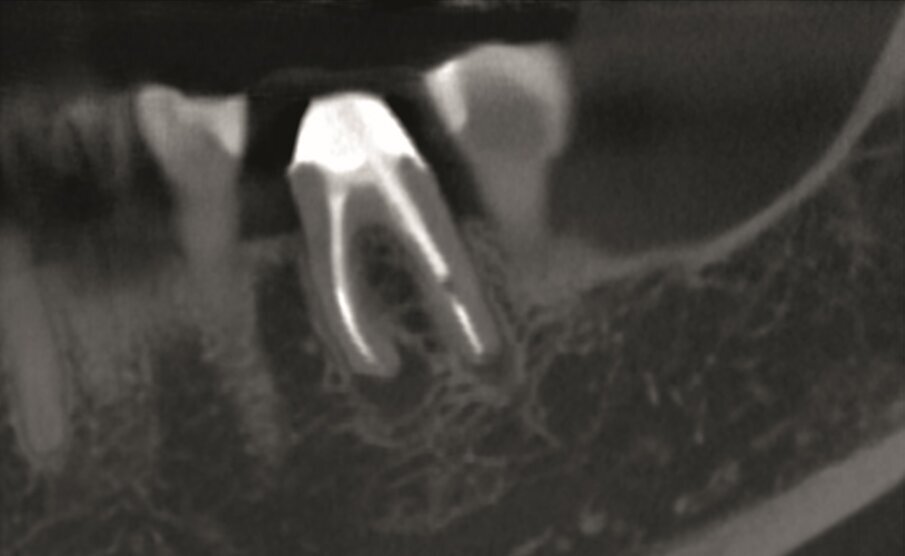

A 38-year-old female patient consulted owing to moderate pain associated with her previously treated maxillary right second premolar. Her medical history was non-contributory. Clinical examination revealed that the tooth was slightly sensitive to vertical percussion. Periodontal probing depth and mobility were within normal limits. A periapical radiograph showed the presence of a separated instrument outside of the root (Fig. 2a), and a preoperative CBCT scan demonstrated that the buccal bone plate was intact (Figs. 2b & c). Endodontic retreatment had been performed five months earlier. The diagnosis for tooth #15 was previously treated symptomatic periapical periodontitis, and the treatment of choice was guided EMS.

An intra-oral scan (TRIOS) of the maxilla, and the resulting STL file (Fig. 2d) was combined with the DICOM files of the CBCT scan to plan a surgical guide using the Zirkonzahn. Implant-Planner software (Zirkonzahn) modified with Meshmixer (Autodesk). A template that marked the limits of a cortical window to accurately reach the apical area was designed and printed (Figs. 2e & f).

Under local anaesthesia, a full-thickness mucoperiosteal‑ap was reflected, providing visualisation of the buccal bone (Fig. 2g), and the printed template was used to mark the cortical window (Fig. 2h), which was cut with a Piezotome CUBE LED handpiece, and the separated instrument was exposed (Fig. 2i) and removed (Fig. 2j). After apicectomy, retro-preparation was done using ultra sonic tips (ACTEON) and sealed with TotalFill BC RRM Fast Set Putty (FKG) (Fig. 2k). The ‑ap was sutured using 5/0 prolene suture material (Fig. 2l). The sutures were removed 72 hours postoperatively. After two years the patient came to our office for a follow-up radiograph, the tooth was asymptomatic and in function (Fig. 2m).

Fig. 2m: Two years follow-up radiograph.